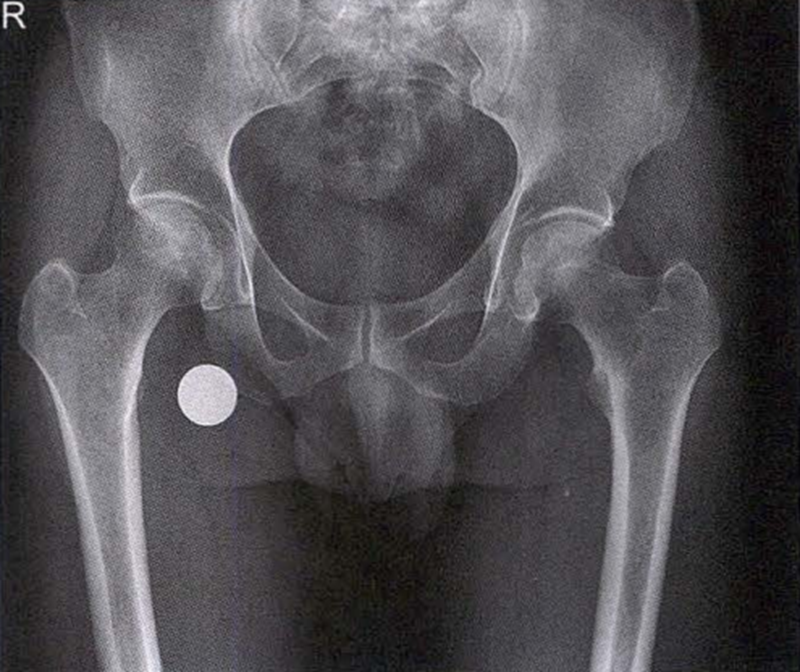

X线检查示右侧股骨头骨质密度不均匀

A.男性,71岁,双侧股骨头坏死,右侧Ⅰ期、左侧Ⅲ期。X线片示双侧股骨头形态可,右股骨头未见明显密度改变,左股骨头关节面下见局限性骨密度减低及增高区(A1)。MRI(T2加权像)示右股骨头内双线征,左侧不规则形混杂信号,坏死区远端骨髓水肿(A2、A3)。

B.男性,31岁,双侧股骨头坏死,双侧均为Ⅲ期。X线片示双侧股骨头密度不均、股骨头稍变扁(B1)。MRI(T1加权像)示股骨头内多发不规则信号带(B2),股骨头内凸向大转子的双线征(白色箭)和软骨下骨骨折(白色三角)。